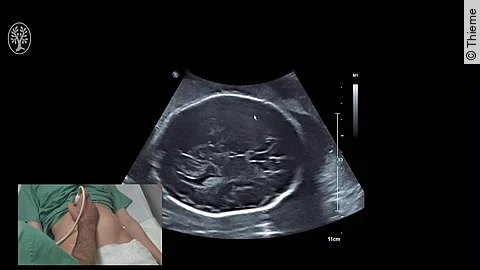

Nehmen Schwangere die Bewegungen ihres Kindes im Mutterleib weniger wahr, wird dies nicht immer ernstgenommen und überprüft. Dabei ist das Risiko für schwere Komplikationen hoch und eine schnelle Abklärung notwendig.

Für Sie operierte PD Dr. Markus Hoopmann aus dem Department für Frauengesundheit Tübingen. Es moderierten: Prof. Dr. Bernhard Krämer und OA Dr. Felix Neis.